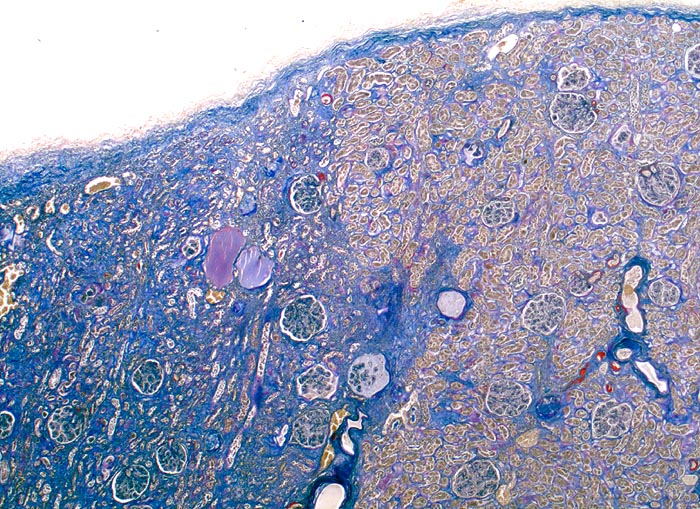

Subinfarkt

Systemerkrankung/Immunpathologie

Niere

Niere, Harnwege

Diabetes mellitus Typ II und arterielle Hypertonie seit 10 Jahren. Leichte Proteinurie.

Als Folge stenosierender Gefässveränderungen kommt es zu fokaler ischämischer Atrophie der Nierenrinde (Subinfarkt) gekennzeichnet durch eine tubuläre Atrophie und interstitielle Fibrose.

Histologie

25

74